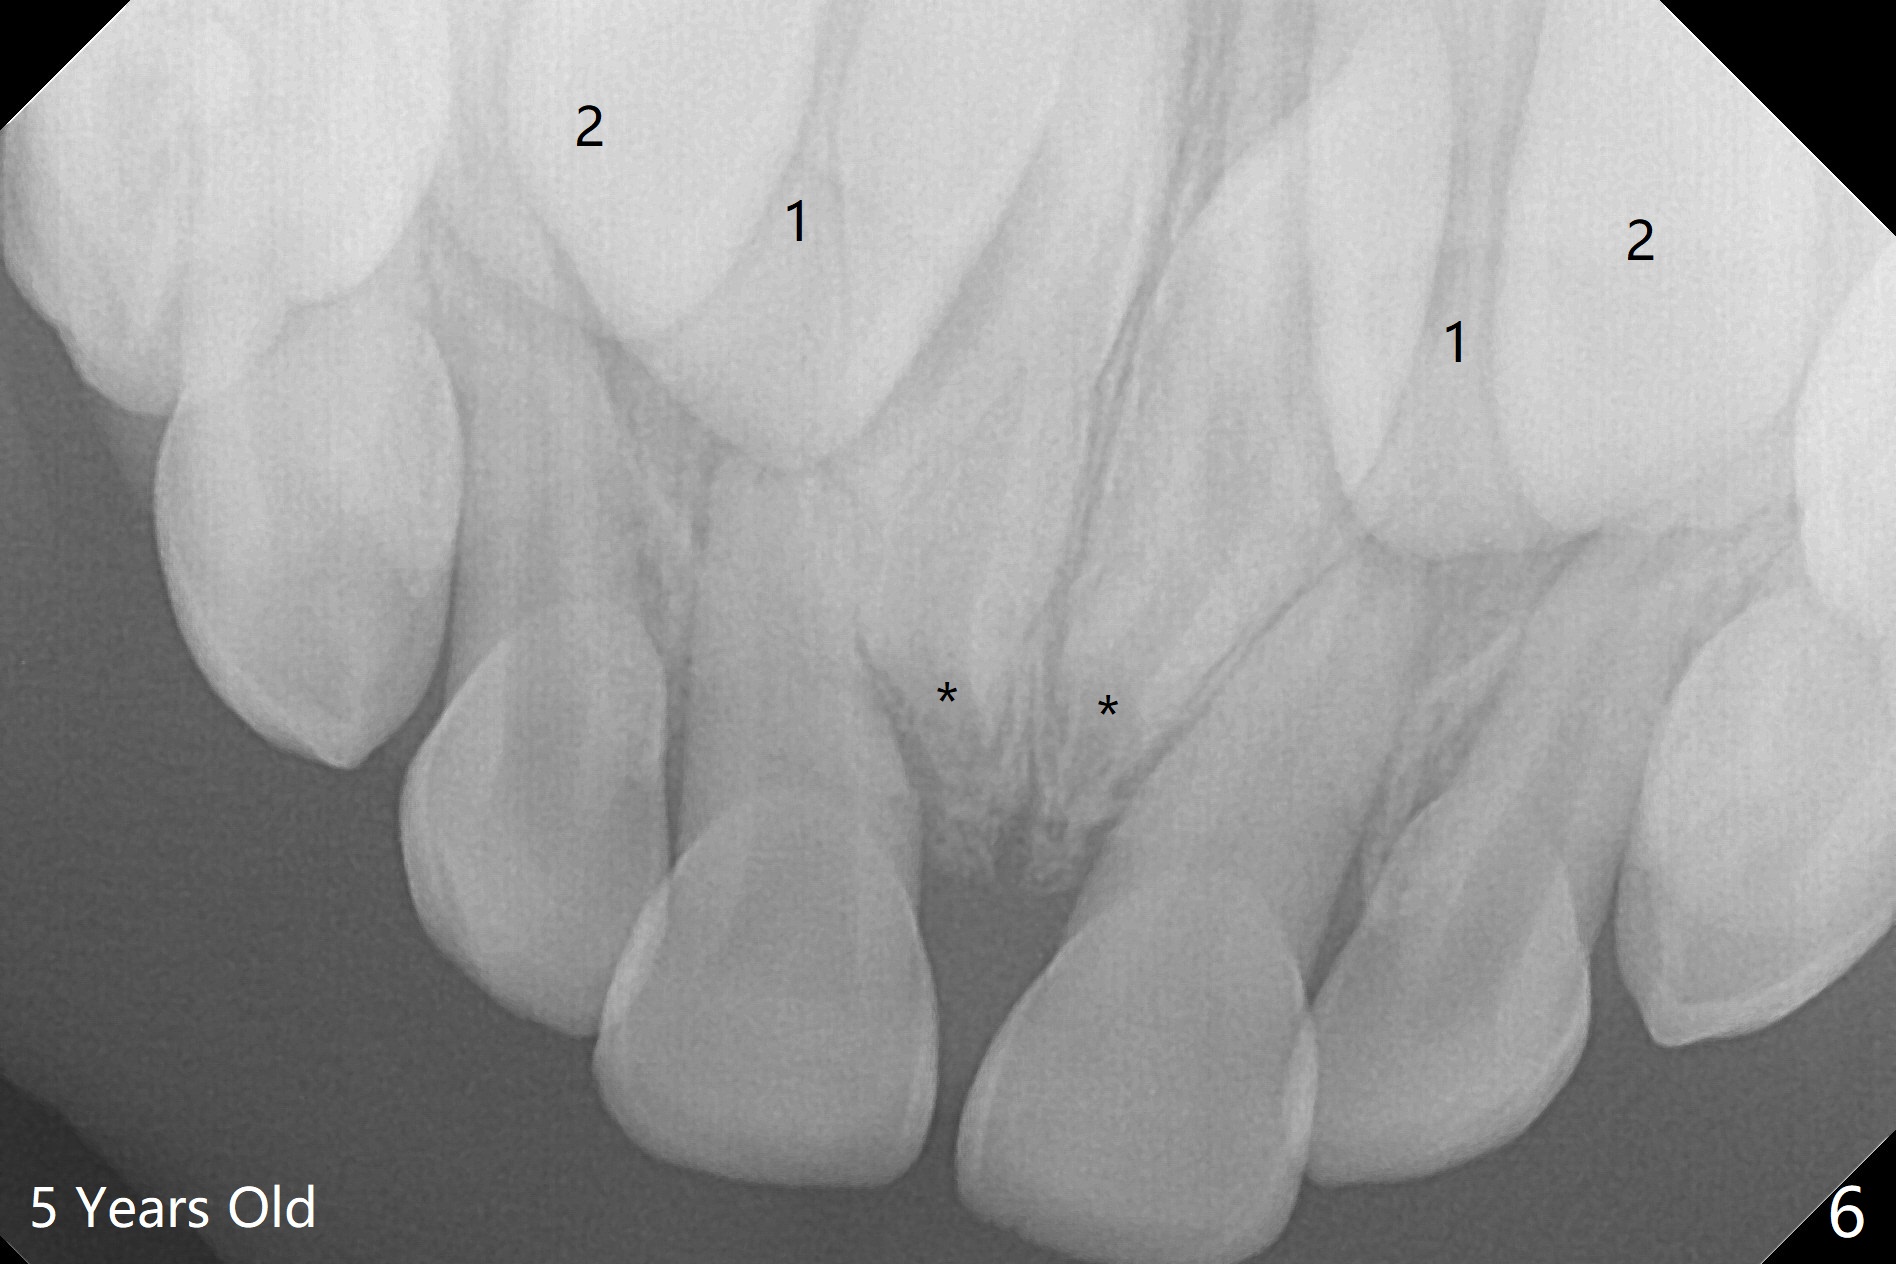

A 3-year-old boy with attention deficit and autism has several incipient caries.  Panoramic X-ray reveals that two of mesiodens (Fig.1 *) block eruption of the upper central incisors (1), as compared to the lateral ones (2).  When is the best time to extract the mesiodens?

PA is taken 10 months later (Fig.5).  The roots of the supernumerary teeth (*) elongate, while the permanent centrals (1) have descended as the same level as the laterals (2).  The divergent centrals seem not be able to cause root resorption of the deciduous ones.  The parents have hesitated to accept surgical removal.  This PA (Fig.6) is taken 6 months later (as compared to Fig.5).  The apices of the supernumerary teeth (*) appear to have closed, while the permanent centrals (1) remain as the same level as the laterals (2).  The divergent centrals seem not be able to cause root resorption of the deciduous ones.  The patient is superactive.